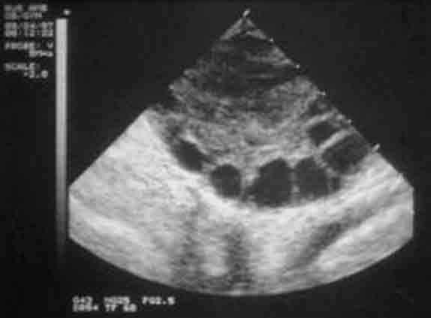

成熟卵泡的B超表现:

1、卵泡呈圆形或椭圆形,直径达15-30mm(21.2+-0.53mm),卵泡内呈无回声区,清亮纯净,边界清晰,壁菲薄。

2、20%成熟卵泡在排卵前一天,可见卵丘图像,在卵泡内近壁处呈短强回声。